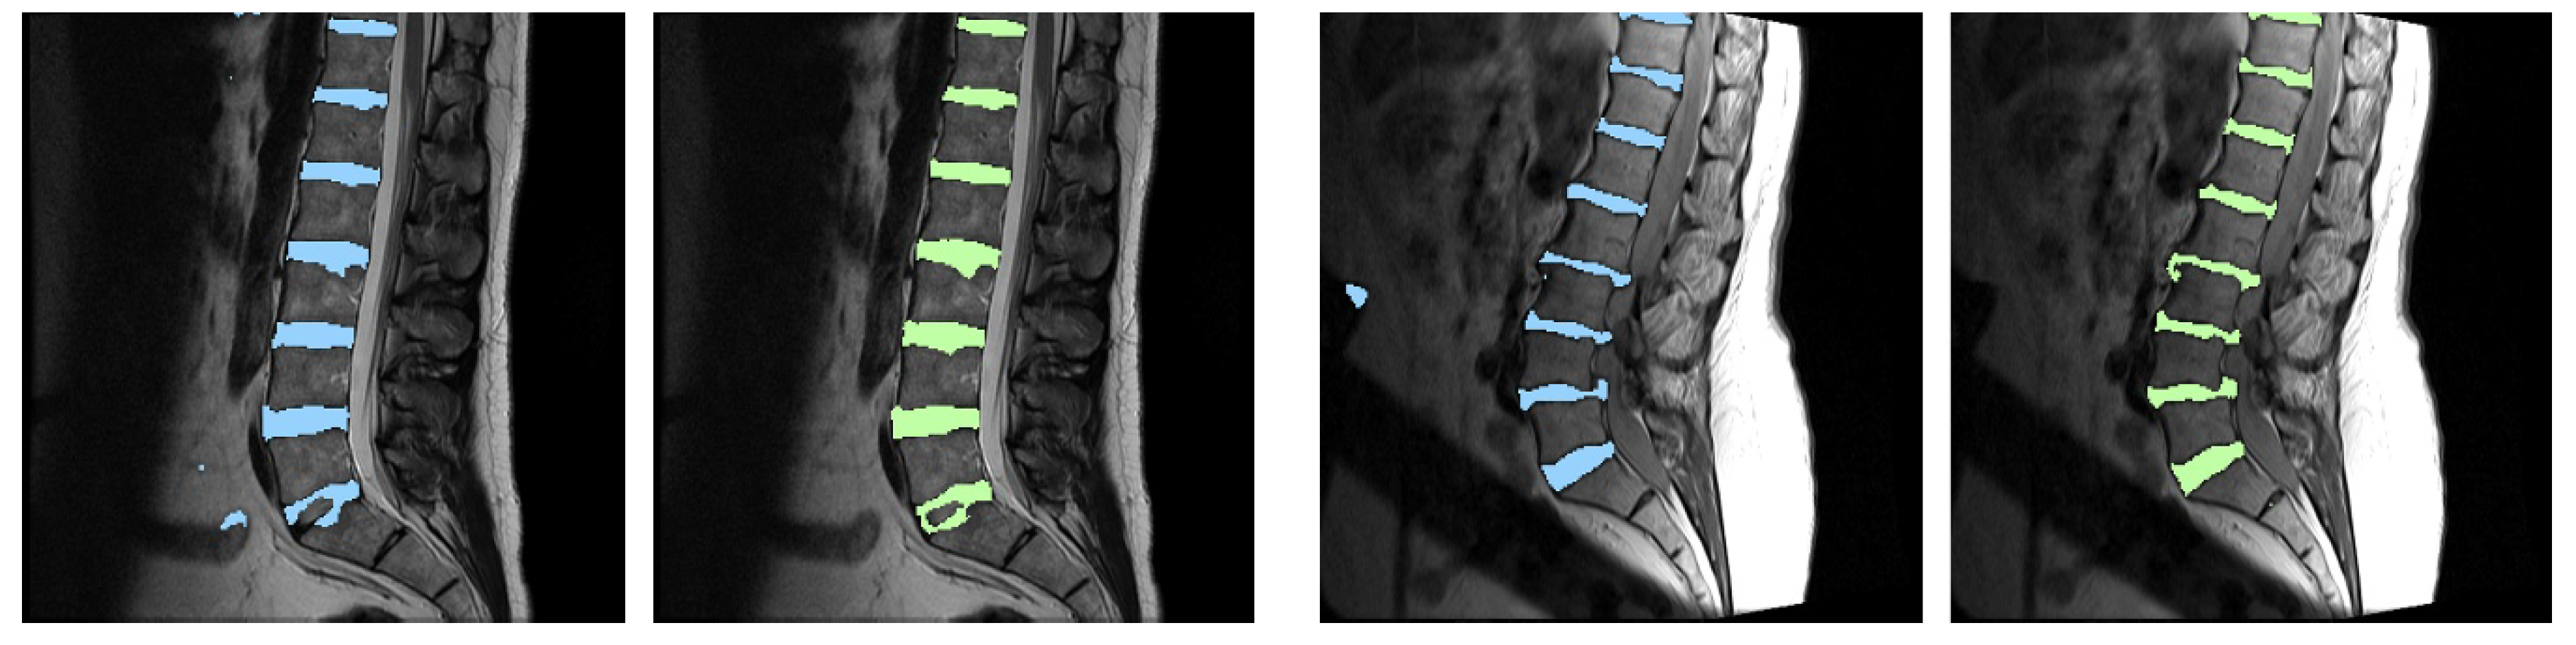

Fine-Grain Segmentation of the Intervertebral Discs from MR Spine Images Using Deep Convolutional Neural Networks: BSU-Net

2.1. Network Design: Boundary Specific U-Network (BSU-Net)